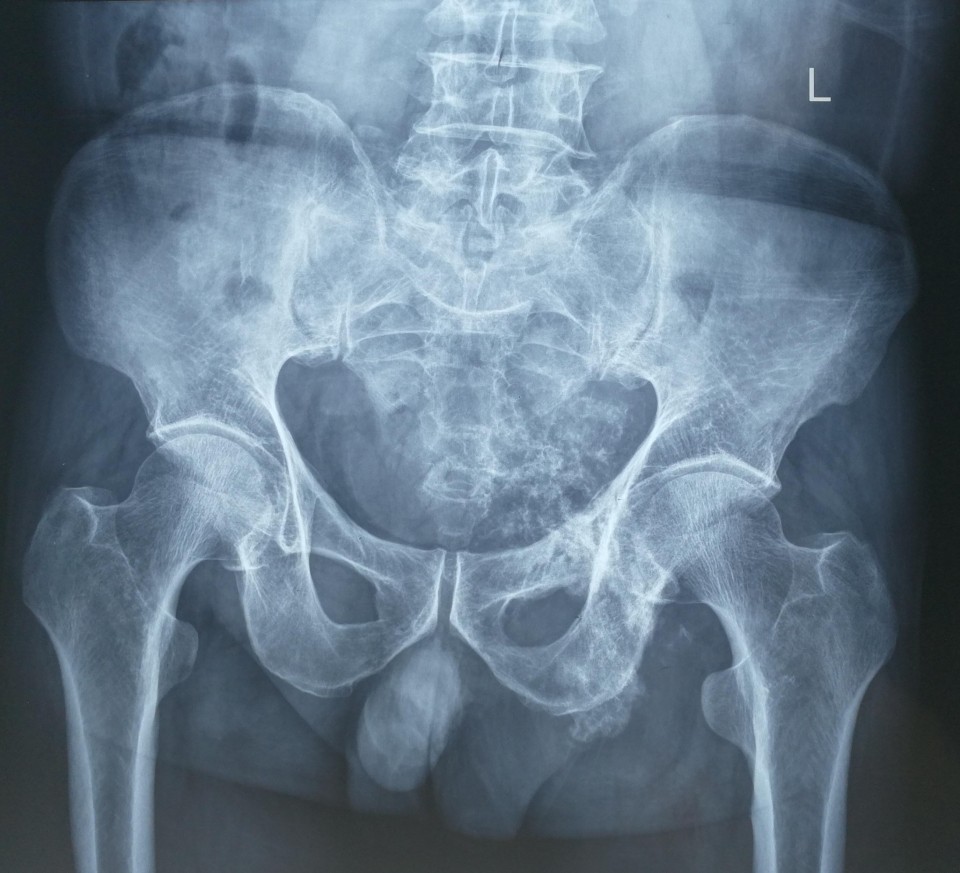

日前,骨病骨肿瘤科近日完成 “骨盆Ⅱ+Ⅲ区巨大软骨肉瘤行内半骨盆切除+股骨头旷置术的保肢治疗 ”1例。患者66岁男性,髋部疼痛不适3月余入院,经检查提示骨盆Ⅱ+Ⅲ区巨大恶性骨肿瘤。骨盆的恶性肿瘤,往往就诊时肿瘤已经发展了相当长的时间,而肿瘤巨大、术中出血多、局部解剖结构复杂等因素使得手术难度及风险增高。早年对骨盆恶性肿瘤的治疗,半骨盆截肢术是骨盆恶性肿瘤的主要治疗方式。但患者所承受的心理压力巨大,面对肢体残缺所引起的恐慌使其拒绝接受治疗,尤其对于年轻患者。保肢术的开展及应用为这些患者带来希望,但手术难度极大,不易达到安全的外科边界。胡勇教授团队根据患者病情,制定精细手术方案,多套手术预案,由于患者经济条件不佳,使用人工关节假体会造成患者极大负担,而且如果出现并发症需要治疗,更导致花费巨大。采用内半骨盆切除+股骨头旷置术,术中既完整的切除了肿瘤,又保全了半侧肢体,辅助术后功能锻炼,几乎可以达到与人工假体相媲美的肢体功能。患者术后顺利康复出院。

胡勇教授指出,骨盆肿瘤的规范化治疗中,肿瘤的完整切除在其治疗中占重要地位,由于骨盆位置深在,血管神经、肠道泌尿道毗邻,骨盆肿瘤的完整切除手术难度极大,技术要求高。对于肢体的重建,虽然人工假体并发症多、价格高昂,但能提供患者相对较好的髋关节功能,肢体长度和外形较满意,故对于大多数患者来说,只要局部软组织重建条件允许骨盆人工关节置换仍是首先考虑的重建方法。该患者由于经济原因不能承受人工假体高昂的费用支出,我们手术尽量保留髋臼顶部骨量,将股骨头置于该处,后期形成假关节可替代原髋关节保留行走功能。一些学者经过长期随访研究,认为旷置成形术避免了很多严重并发症,而且创建了一个无痛且有中等程度功能的肢体。类似骨盆肿瘤的手术我科已开展多例,均取得良好疗效。